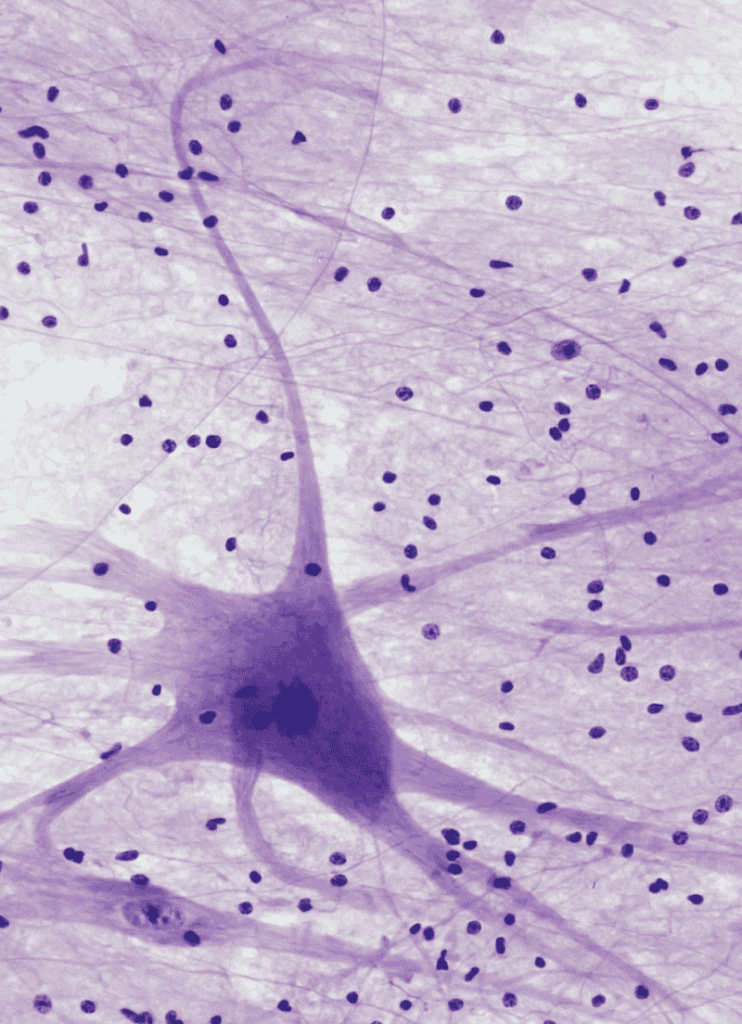

Exosomes in Intercellular Communication

Exosomes are small extracellular vesicles, typically ranging from 30 to 150 nm, that play a critical role in intercellular communication. They carry proteins, nucleic acids, and lipids, effectively transmitting signals between various cell types. Secreted by multivesicular bodies through exocytosis, these vesicles facilitate communication across different cell types and tissues.

Exosome biogenesis involves complex mechanisms, including both ESCRT-dependent and independent pathways. The diverse cargo selection highlights their potential for specificity in delivery. Notably, neural progenitor cell-derived exosomes aid in neurogenesis and differentiation, emphasizing their involvement in nervous system signaling.

Their Role in Cell Signaling

Exosomes are pivotal in mediating cell signaling by transferring signaling molecules such as proteins and nucleic acids to recipient cells. This can modulate various physiological functions, for instance, enhancing GLT1 expression in astrocytes through miRNA transfer. The cell type of origin and physiological state influence the exosomal cargo, subsequently impacting gene expression and cellular processes like proliferation and differentiation.